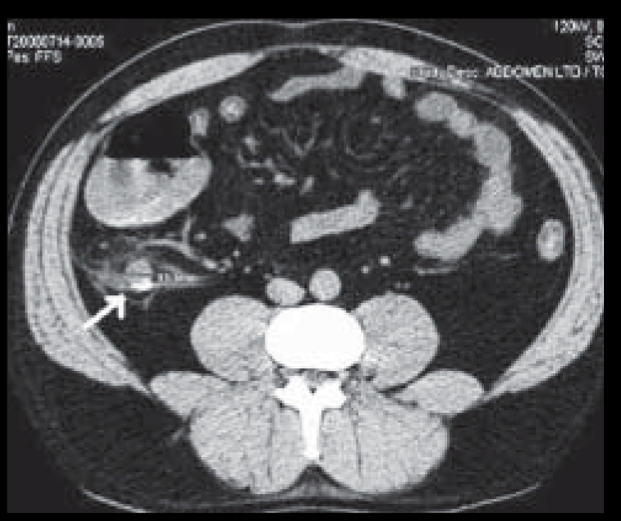

Q

que se ve en tc

A

apendice distendida

Grasa sucia

Apendicolito

Realce con contraste

19

que otra cosa nos permite ver tc

absceso

Perforacion